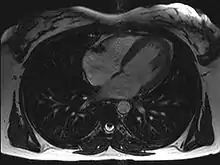

Magnetic resonance imaging (MRI)

Magnetic resonance imaging visualises the heart by detecting hydrogen atoms using superconducting magnets, particularly those attached to water and fat molecules.[3] These hydrogen atoms possess a property known as nuclear spin. Although the direction of this spin is usually random, the spin can be aligned using a powerful magnetic field.[3] Faint electromagnetic signals are emitted by these hydrogen atoms when their alignment is temporarily disturbed which can be detected and used to create an image of the heart.[4]

MRI is able to measure the size, shape, function, and tissue characteristics of the heart in a single session.[5] It is more reproducible than echocardiography with less inter-observer variability, allowing for more precise reference ranges to better distinguish health from disease.[5] Additional benefits from cardiac MRI include the ability to detect scar within the heart using late gadolinium enhancement, and identify other abnormalities of the heart muscle itself such as infiltration with iron or amyloid protein.[5] Disadvantages of MRI include lengthy protocols and the potential for claustrophobia. Furthermore, an MRI scan cannot be performed in some people who have metallic implants such as some types of pacemakers, defibrillators, although many modern pacemakers are safe for use within an MRI scanner.[6] Other metal structures such as artificial valves and coronary stents are generally not problematic.

Recent development in deep learning and convolutional neural network techniques have made it possible to analyze and quantify some aspects of cardiac MRI automatically.[7] The use of cardiac MRI is projected to increase through greater availability of scanners and more widespread knowledge about its clinical application.